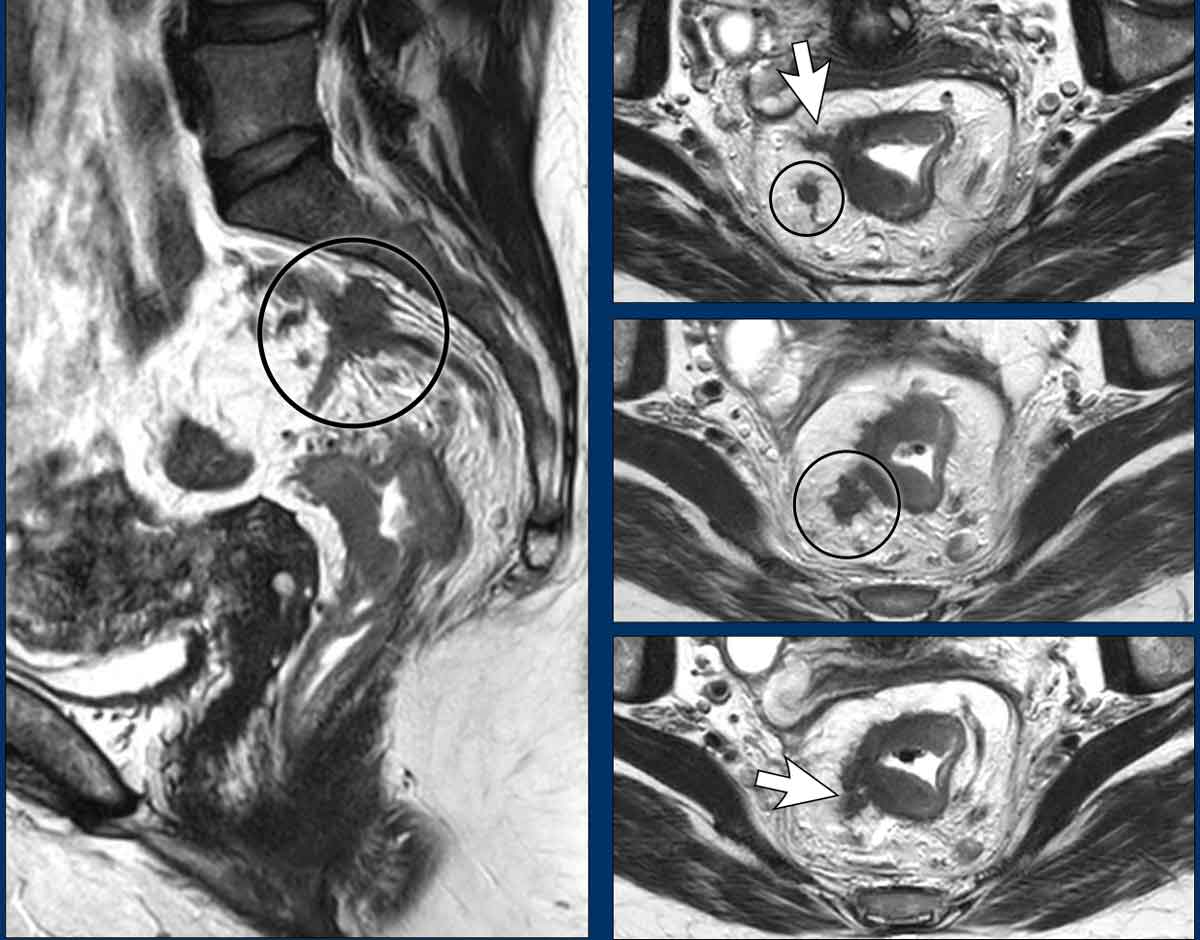

Polypoid and Sessile tumors

Rectal adenocarcinomas usually originate from adenomas, which may be:

• Polypoid: Raised on a stalk or focal attachment, often low-grade (T1–T2), projecting into the lumen.

• Sessile: Flat, broad-based, typically presenting as partial or complete annular wall thickening.

Invasive Margin: The tumor’s attachment site to the rectal wall—the invasive margin—is the site where the tumor may invade beyond the rectal wall, and is therefore critical for T-staging and assessing extramural extension.

Tumor Circumference: Describe the degree of wall attachment in the report using either:

• Clock-face notation (e.g., “from 3 to 7 o’clock”)

• Prose (e.g., “left anterolateral”).